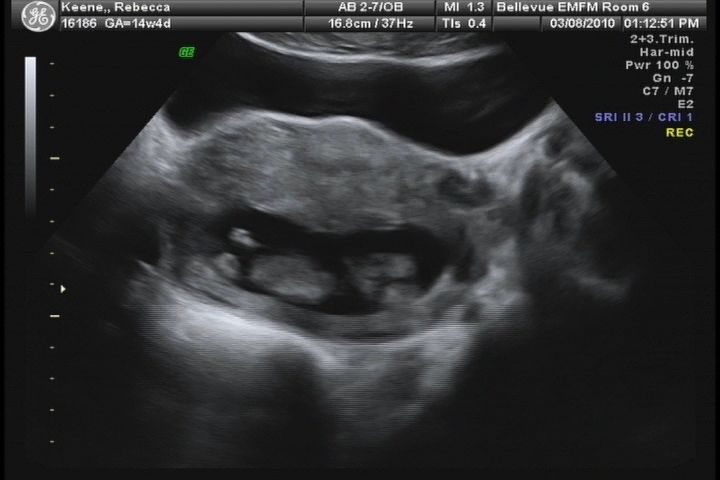

We had our screening appointment today for birth defects, and with it came a wonderful ultrasound. We got some great pictures, and even a DVD. I pulled some of the footage off the video to make a short clip movie – below.

The baby is healthy and strong. We heard the heart beat (160 bpm) and saw Baby 2 hiccupping! Since we believe that it’s a boy, we’re going to continue with “he” instead of “baby 2.”